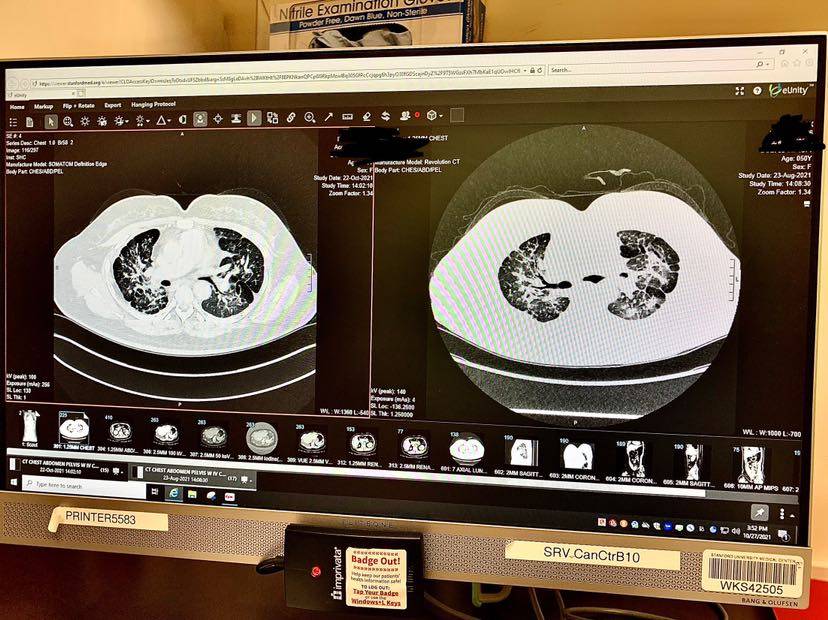

最近的这个月我又出现了气短,上楼梯、提一点重量的东西走路都出现了短暂的缺氧88-90,但是休息一下1-2分钟又回复到正常的97-96。所以告诉医生后又要我拍CT,CT结果医生说对比2个月之前的好了很多,我都不懂看,反正这个结果我也没有什么好高兴的,因为还是解释不了为什么我会气短?医生说暂时先不要换药,观察一下,如果气短加重有及时告诉她们,反正现在能吃、能喝、能睡,正常生活,所以也没有想太多,现在我是佛系态度去对待我的病,该干什么就干什么,做自己喜欢的事就好!下面的图片左边👈是10月22号拍的,右边👉是8月23号拍的对照图片。